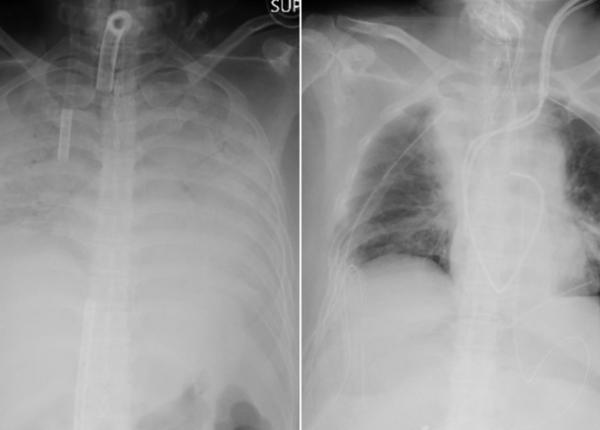

Prof dr Constantin Ionescu-Târgoviște a vorbit la emisiunea Academia de Sănătate, realizată de profesorul Irinel Popescu, despre problemele pacienților cu diabet în timpul pandemiei COVID-19....